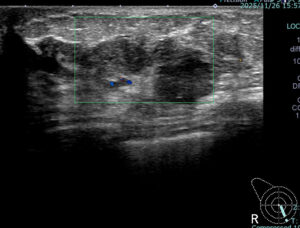

このエコー像では「おそらくセンチネルリンパ節生検は陰性だろう」となる。

実際の手術病理では 20/24

術前エコー(1か月前)